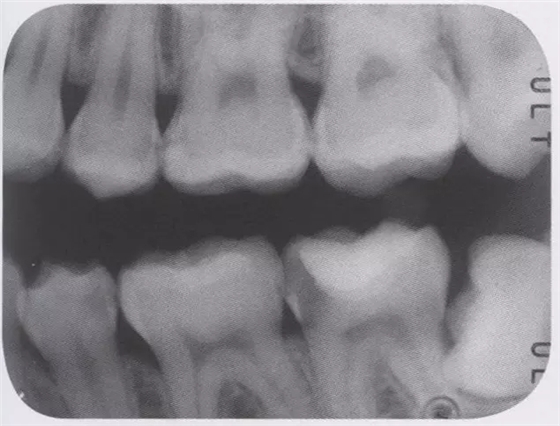

圖3 全瓷嵌體的修復(右56)。鄰接面產(chǎn)生齲齒的情況(上段,中段左),去除齲齒,并佩戴嵌體(下端)。